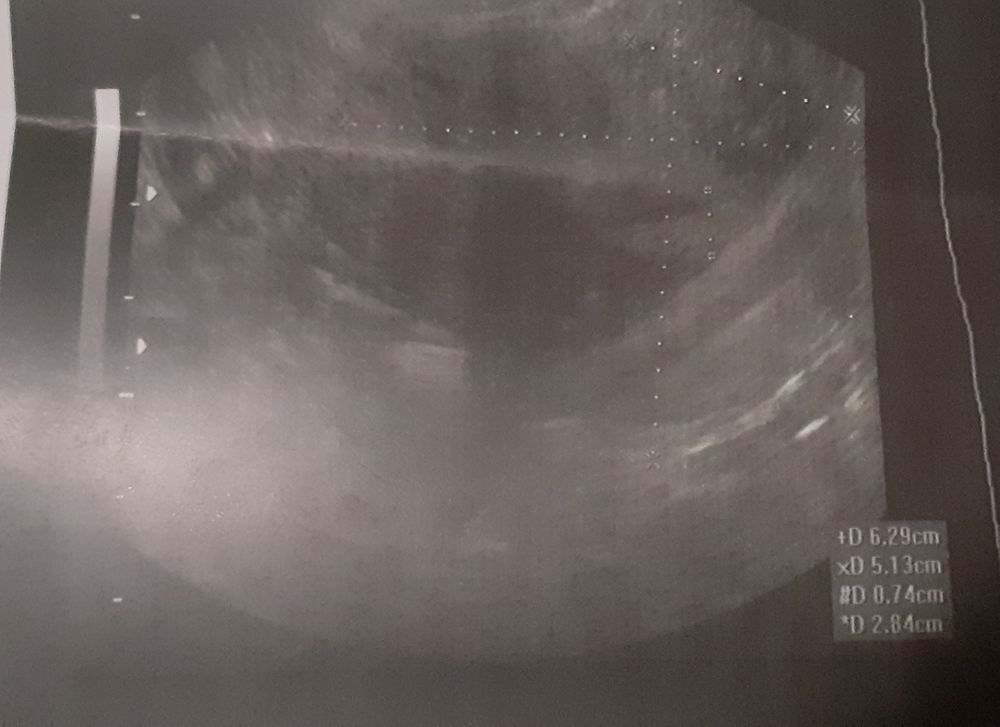

Миома.

Гинекологические заболеванияВрач написал заключение - миома 29 мм. Рассматриваю снимок, сравниваю с рез-т запроса "как выглядит миома на узи" и ни фига сходства не нахожу.

Кто разбирается в УЗИ, посмотрите пожалуйста это миома или нет?

К вопросу миомы врачи не ошибаются. Миомы всегда точно видят. Это не полип - который могут видеть и не видеть и не хронический эндоцервицит. ТАк что заключение ваше правильное. Могут ошибаться только в размерах. Зависит от аппарата, на котором смотрят, и расположения миомы конечно...